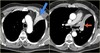

What pathology is seen here?

Pulmonary Embolism (PE) ## Footnote -Filling defect seen -As the vessels get smaller it will occlude the whole thing

163

What pathology is seen here? What are the arrows pointing to?

Pulmonary Embolism (PE) Red arrows: Areas with less signal